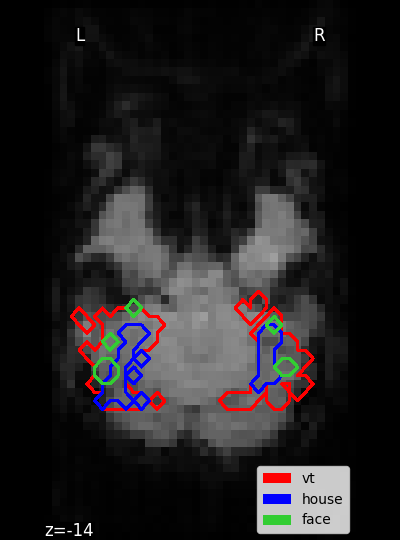

Small script to plot the masks of the Haxby dataset.

Plot the masks¶

mask_vt_filename = haxby_dataset.mask_vt[0]

mask_house_filename = haxby_dataset.mask_house[0]

mask_face_filename = haxby_dataset.mask_face[0]

masks = [mask_vt_filename, mask_house_filename, mask_face_filename]

colors = ["red", "blue", "limegreen"]

for mask, color in zip(masks, colors):

display.add_contours(

mask,

contours=1,

antialiased=False,

linewidth=4.0,

levels=[0],

colors=[color],

)

p_v = Rectangle((0, 0), 1, 1, fc="red")

p_h = Rectangle((0, 0), 1, 1, fc="blue")

p_f = Rectangle((0, 0), 1, 1, fc="limegreen")

plt.legend([p_v, p_h, p_f], ["vt", "house", "face"], loc="lower right")